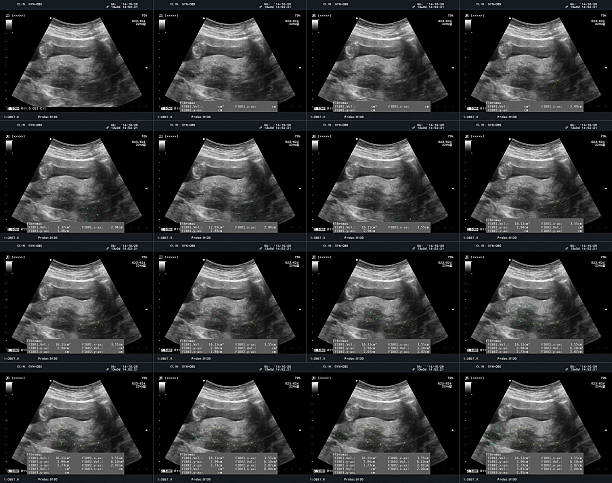

자궁근종은 자궁 내부나 외부에 발생하는 양성 종양으로, 자궁근육 내부에서 발생하는 경우가 가장 많습니다. 자궁근종은 여성들의 월경기에 더욱 빈번하게 발생하며, 대부분의 경우는 악성 종양으로 전이되지 않습니다.

자궁근종은 대개 증상이 없어서 여성들이 모르고 지나칠 수 있습니다. 그러나 종양이 커지거나 수가 많아지면 자궁근육을 압박하거나 옆에 있는 장기를 압박할 수 있습니다. 이러한 압박은 복통, 가끔 출혈, 배뇨 불편 등의 증상을 일으킬 수 있습니다.

자궁근종은 악성종양으로 전이되는 경우는 매우 드뭅니다. 그러나 자궁근종이 크거나 불규칙한 형태를 띄는 경우, 특히 빠르게 성장하거나 원래 크기보다 커진 경우에는 악성종양의 가능성을 염두에 두어야 합니다. 이러한 경우에는 추가적인 검사가 필요합니다.